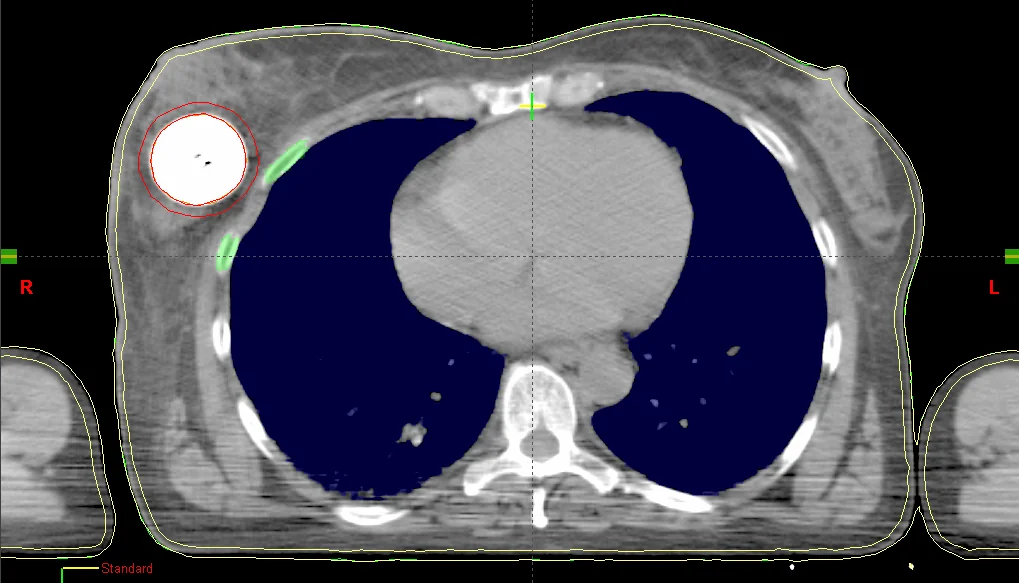

Der MammoSite-Applikator ist ein füllbarer sphärischer Silikonballon, der intraoperativ in der Kavität des entfernten Tumors platziert wird. Der wird Ballon wird mit einem Gemisch aus isotoner Kochsalzlösung 0,9 % und Kontrastmittel (z. B. in einem Verhältnis von 10:1) gefüllt. Das iodhaltige Kontrastmittel hebt den Ballon auf den CT-Bildern vom Brustgewebe ab, sodass er für die Bestrahlungsplanung gut konturiert werden kann. Eine zu hohe Kontrastmittelkonzentration (Empfehlung: <10 %) kann bei Berechnungen mithilfe des TG-43-Algorithmus, der zur Berechnung eine reine Wasserumgebung annimmt, zu großen Dosisabweichungen führen. Das liegt vor allem an dem hohen Iodgehalt in den Kontrastmittellösungen, das aufgrund seiner hohen Dichte zu Dosisreduzierungen führen kann, die vom TG-43-Algorithmus nicht berücksichtigt werden. In mehreren Sitzungen wird die Quelle durch einen Zweikanal-Katheter in den Ballon gefahren. Der Durchmesser des Ballons variiert je nach Patient und Ausführung des Ballons. Um den hohen Ansprüchen komplexer Dosisverteilungen gerecht zu werden, gibt es seit einiger Zeit Multilumen-Varianten (nicht sehr verbreitet in Deutschland), die unter Verwendung mehrerer Katheter weitere Haltepositionen ermöglichen.

Nach der chirurgischen Entfernung des Tumors, wird der MammoSite-Applikator eingesetzt und verweilt dort für die gesamte Behandlungszeit (ca. eine Woche). Am zweiten Tag wird ein Planungs-CT gefahren und basierend auf der Anweisung ein Bestrahlungsplan erstellt. In den letzten drei Tagen wird in je zwei Sitzungen pro Tag eine Dosis in einem bestimmten Abstand, in der Regel in 0,5 cm Gewebstiefe bzw. 0,5 cm von der Ballonoberfläche appliziert. Die Haut- und Rippendosis sollten eine Maximaldosis (z. B. 1,5 Gy pro Fraktion) nicht überschreiten, und bilden somit die limitierenden Faktoren der Behandlung. Je nach klinischer Erfahrung, variieren die Dosierungskonzepte und tolerierbaren Maximaldosen in den Risikoorganen.

Sofern in der Computertomographie um den Ballon große Lufteinschlüsse zu sehen sind (z. B. weil die Kavität das maximale Ballonvolumen überschreitet, oder dieser nicht vollständig aufgefüllt wurde) müssen diese ebenfalls berücksichtigt werden, da Dichteinhomogenitäten vom am weitesten verbreiteten TG-43-Algorithmus nicht berücksichtigt werden. Zu diesem bekannten Problem existiert bereits eine Reihe von Publikationen. Diese beschäftigen sich überwiegend mit den Auswirkungen vom Kontrastmittel, von Lufteinschlüssen am und im Ballon und mit dem Umgebungsmedium, dass im TG-43-Formalismus als Wasser angenommen wird, woraus eine erhöhte Rückstreuung resultiert.